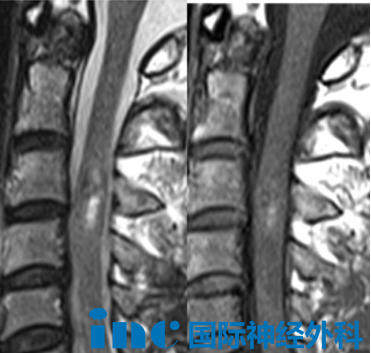

"过年的时候我们全家都吃不下饭,一直担心巴教授能不能过来……"这句简单的话,道出了一家人在过去一个多月里最深的煎熬。今年51岁的潘先生,家庭生活稳定,事业也颇为顺遂,却被身体持续的麻木和酸痛所困。检查结果显示,病根在于颈髓处发生了海绵状血管瘤出血,情况相当凶险。

颈髓是人体中枢神经系统的核心枢纽,其手术涉及呼吸、运动等重要神经功能传导通路,在神经外科领域属于难度极高的术式。手术操作需要在毫米级别的精度范围内完成,以尽可能保护正常神经组织。这对主刀医生的显微解剖能力、操作稳定性以及临场应变水平都有着极严苛的要求。任何细微的操作失误,都可能留下永久性的神经功能损伤,严重时甚至导致瘫痪。

在神经外科领域,巴特朗菲教授以处理高难度脑肿瘤闻名,而在同样充满挑战的脊髓髓内手术方面,他同样拥有深厚的积累。年轻时期,他在正式涉足脑干手术之前,已经完成了大量脊髓髓内手术的临床历练。除了精湛的操作技术外,他还具备一种近乎直觉的"感知能力"——手持双极电凝,能够在看不见的脊髓深处,凭借细微的触感找到肿瘤所在,辨别出肿瘤与正常神经之间那条极细微的边界。正是这种能力,让他在神经外科最复杂的领域持续追求着技术的极致。